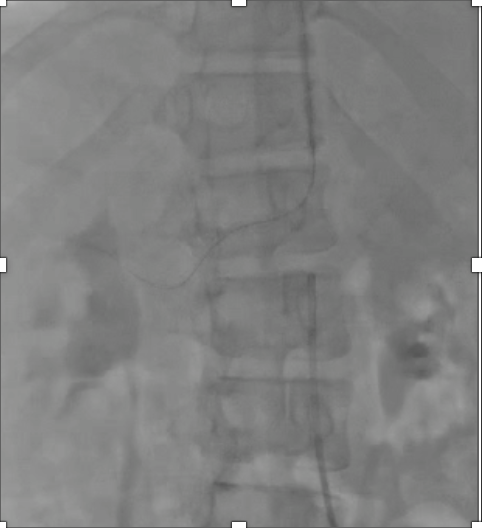

Despite having an overlay from three dimensional three dimensional fusion imaging, it was difficult to wire the right renal artery. Five French right brachial arterial sheath was introduced under ultrasound guided. Polymer jacket coronary guide wire was used under two dimensional three dimensional fusion imaging. Wiring was finally succeeded with the support of JR 3.5/ 5 Fr guiding catheter from the brachial access. Lesion was predilated using 2.0 x 15 mm and 4.0 x 15 mm semi compliant coronary balloons. Drug eluting stent of 4.0 x 15 mm was implanted and post dilated using 4.5 x 12 mm non compliant coronary balloon. The procedure was uneventful. Fluoroscopy time was 53.16 minutes, contrast volume was 130 cc, radiation dose was 83.88 mGy.